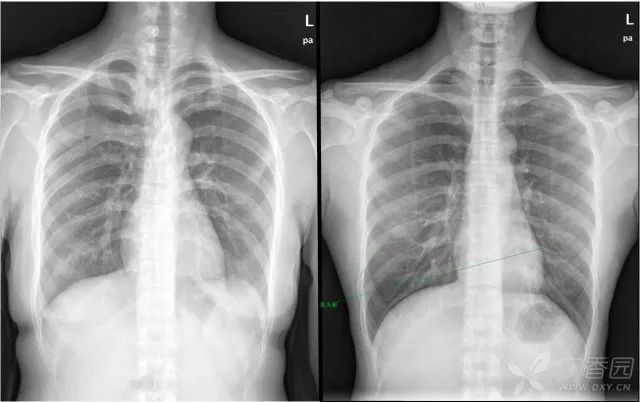

【看图说话】从常规胸片中看出不寻常【有答案】